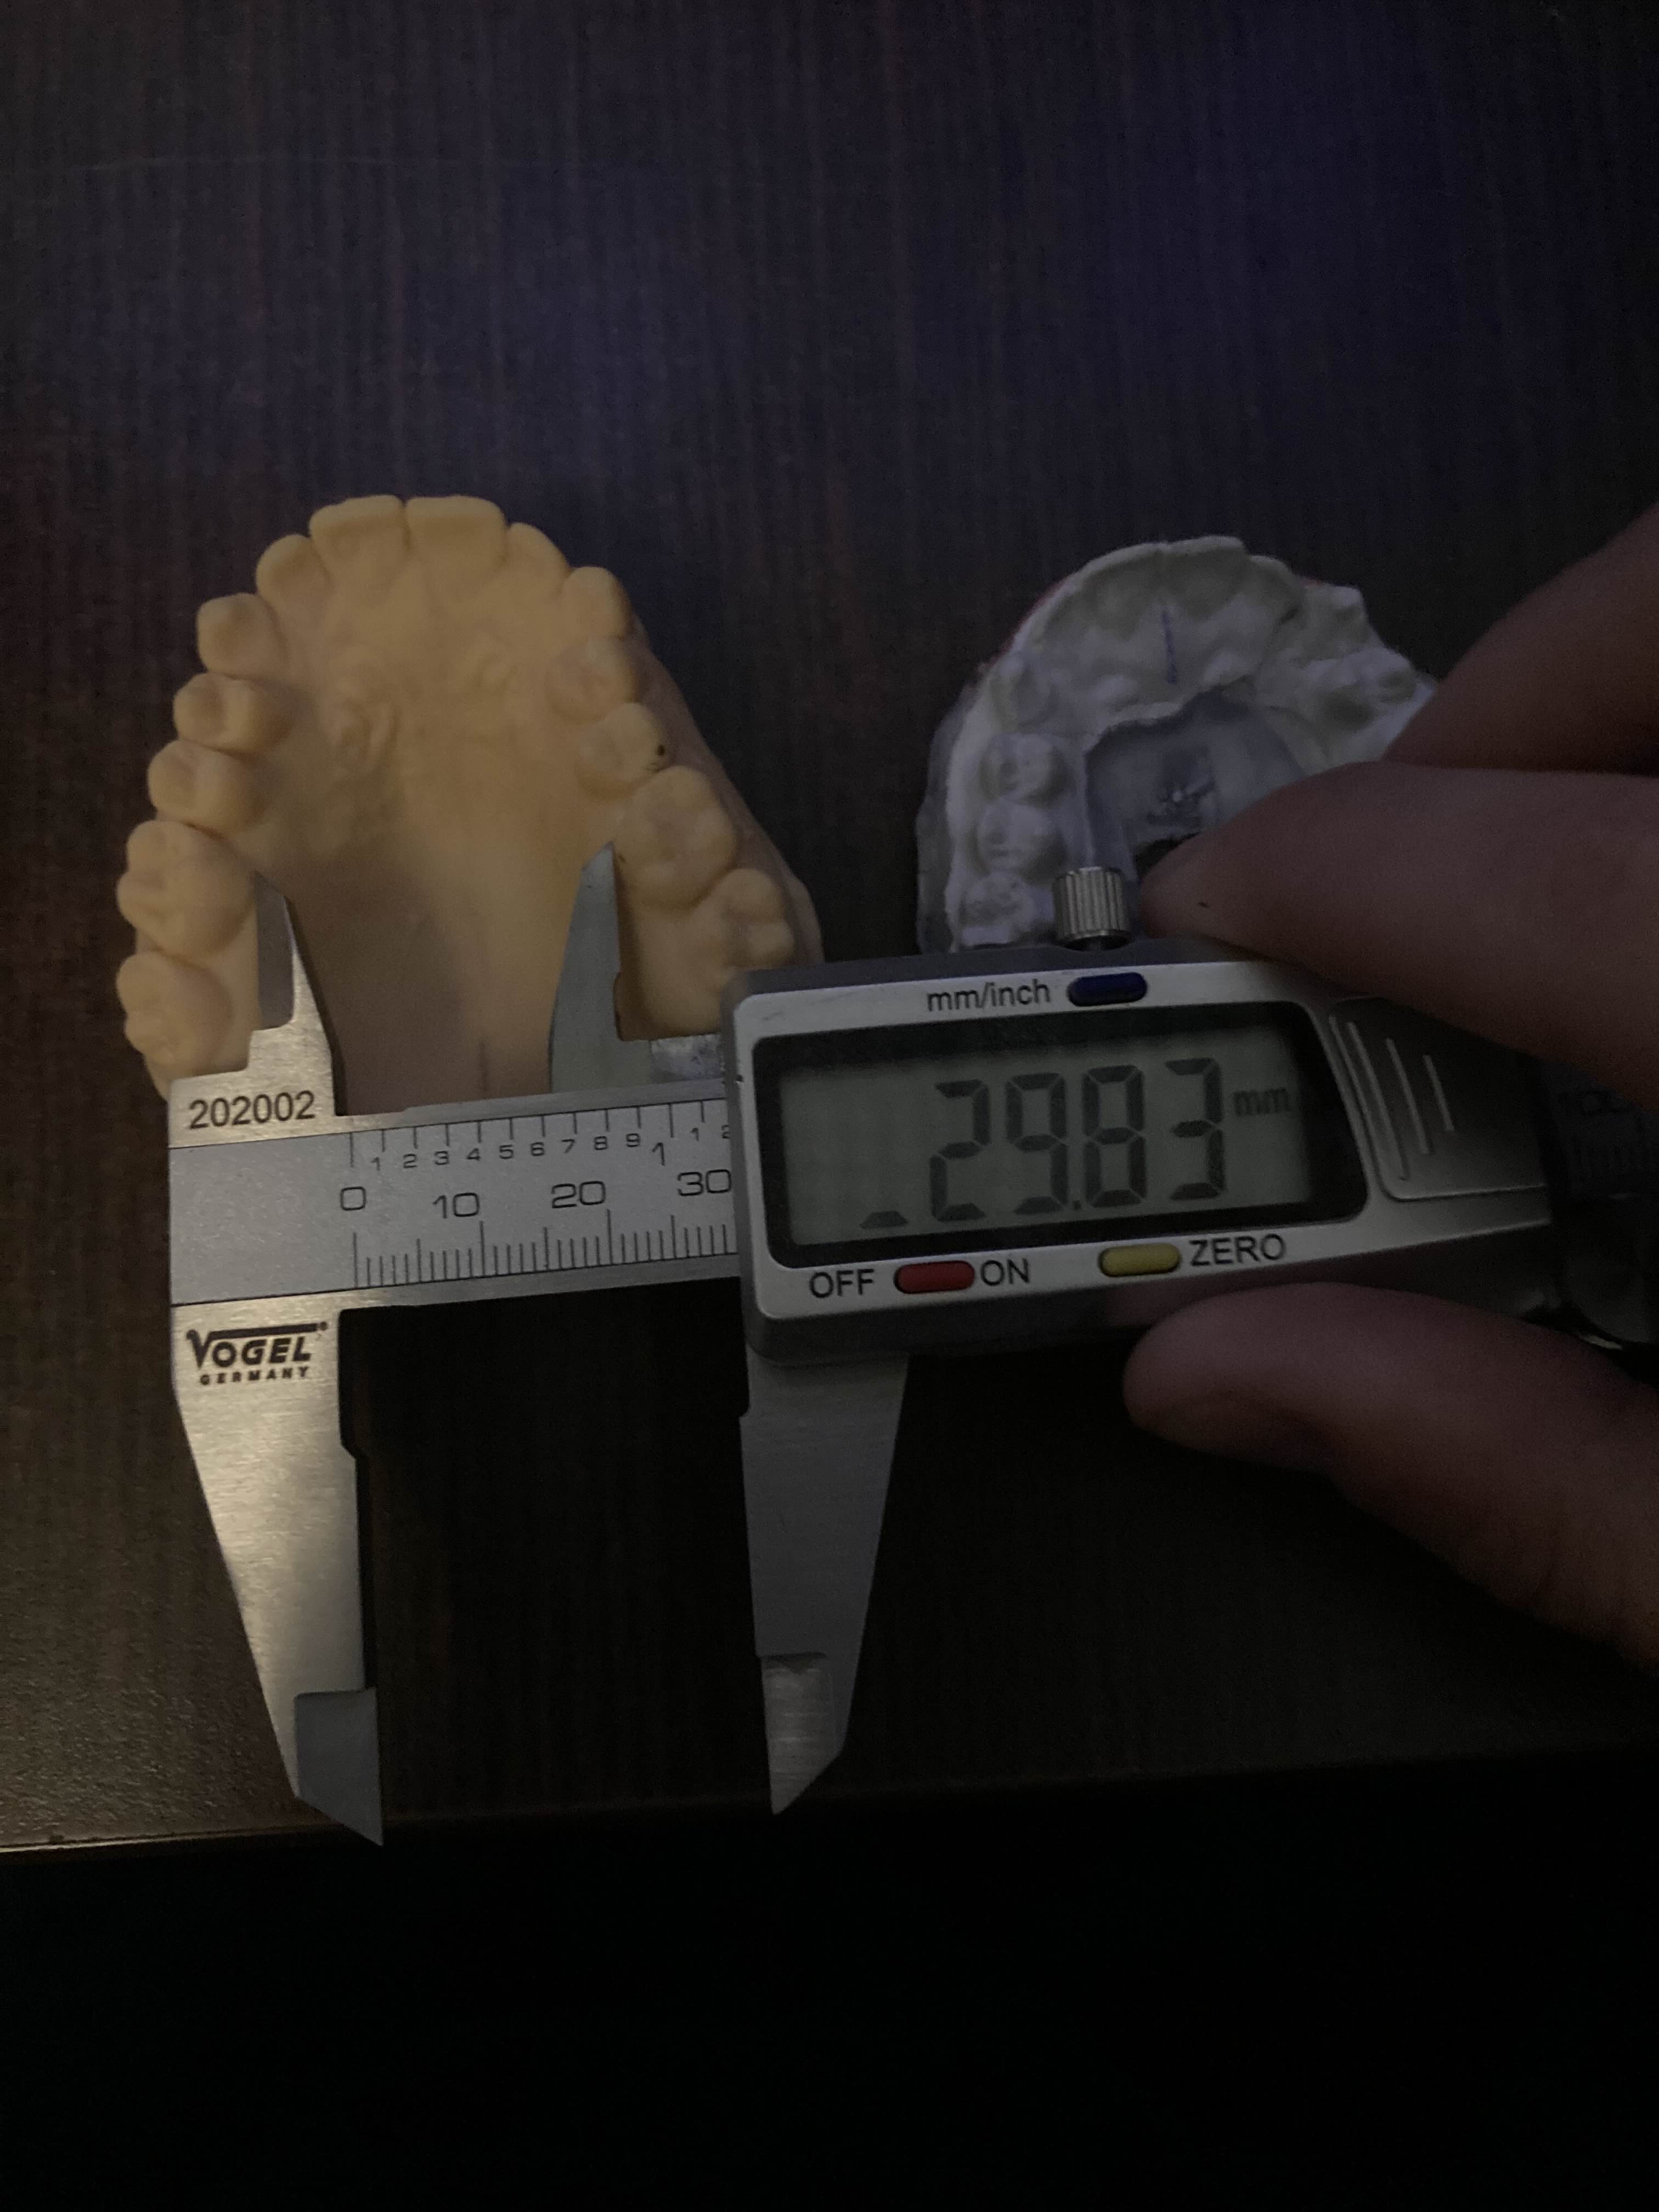

The white mold was made by me the yellow by them very quality stuff I must say

The white mold was made by me the yellow by them very quality stuff I must say